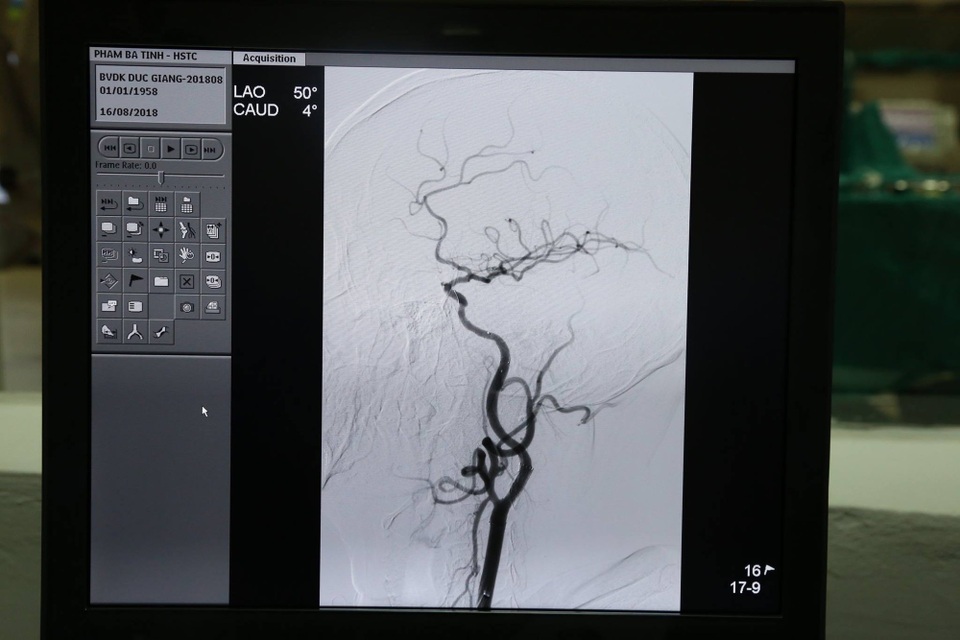

Ca can thiệp cho bệnh nhân diễn ra hôm 16/8, kíp can thiệp của Đơn vị Đột quỵ do bác sĩ Nguyễn Văn Học - khoa Hồi sức chống độc với sự hỗ trợ của TS.Nguyễn Trọng Tuyển (Đơn vị can thiệp mạch – Bệnh viện Trung ương Quân đội 108), đã thực hiện thành công kỹ thuật chụp mạch não, nong đoạn hẹp bằng bóng và đặt stent qua đoạn hẹp cho bệnh nhân bị hẹp khít 90% động mạch cảnh trong bên Trái/ Nhồi máu não lỗ khuyết dưới sự hỗ trợ của máy DSA.